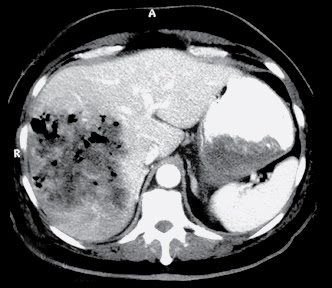

Hepatic abscesses, like abscesses elsewhere, are localised collections of necrotic inflammatory tissue caused by bacterial, parasitic or fungal agents. Introducción: el absceso hepático amebiano es la manifestación . El diagnóstico diferencial se relaciona con absceso piógeno, subfrénico, piocolecisto. Absceso Hepático Amibiano Ha disminuído la frecuencia 25% tienen antecedente de diarrea Más frecuente en hombres Más frecuente en LHD Absceso único.

An Med Interna Madrid ; 5: Si continua navegando, consideramos que acepta su uso. Amoebic abscesses are more common in a sub-diaphragmatic location and are more likely to spread through the diaphragm and into the chest. Rev Esp Enferm Dig ; During the two decades studied, 45 patients were diagnosed with PLA caused by bacteria, and there were 13 cases of ALA.

Eur J Gastroenterol Hepatol, 10pp. It is an aggregation of multiple low attenuation liver lesions in a localised area to form a solitary larger abscess cavity. When the infection spreads to the liver through the portal veins it arises more commonly in the right lobe, probably due to an unequal distribution of superior and inferior mesenteric vein contents within the portal venous distribution.